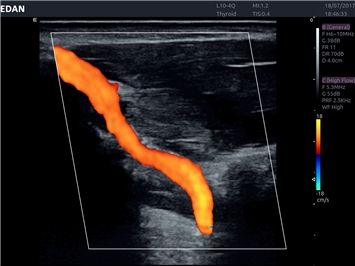

EDAN Acclarix LX4

Расширьте свои представления. Использование усовершенствованной платформой Acclarix система LX4 обеспечивает непревзойденную четкость изображений и интеллектуальный рабочий процесс для всех пользователей, являясь при этом наиболее экономичным решением.

EDAN Acclarix LX4 представляет собой инновационную ультразвуковую систему, построенную на усовершенствованной платформе Acclarix. Сочетание высокого качества визуализации с интеллектуальным рабочим процессом делает эту систему оптимальным выбором для клиник, ценящих эффективность и экономичность.

• Сосудистой диагностики

Цветовой допплер:

Да